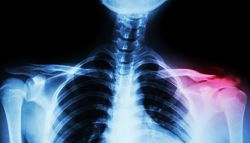

Gãy xương đòn là một dạng chấn thương phổ biến, đặc biệt là ở trẻ em và thanh niên. Xương đòn hay xương quai xanh là hai xương nối phần trên của xương ức với xương bả vai. Các nguyên nhân phổ biến gây gãy xương đòn gồm có ngã, chấn thương do tai nạn giao thông và chấn thương do chơi thể thao. Trẻ sơ sinh có thể bị gãy xương đòn trong quá trình sinh.